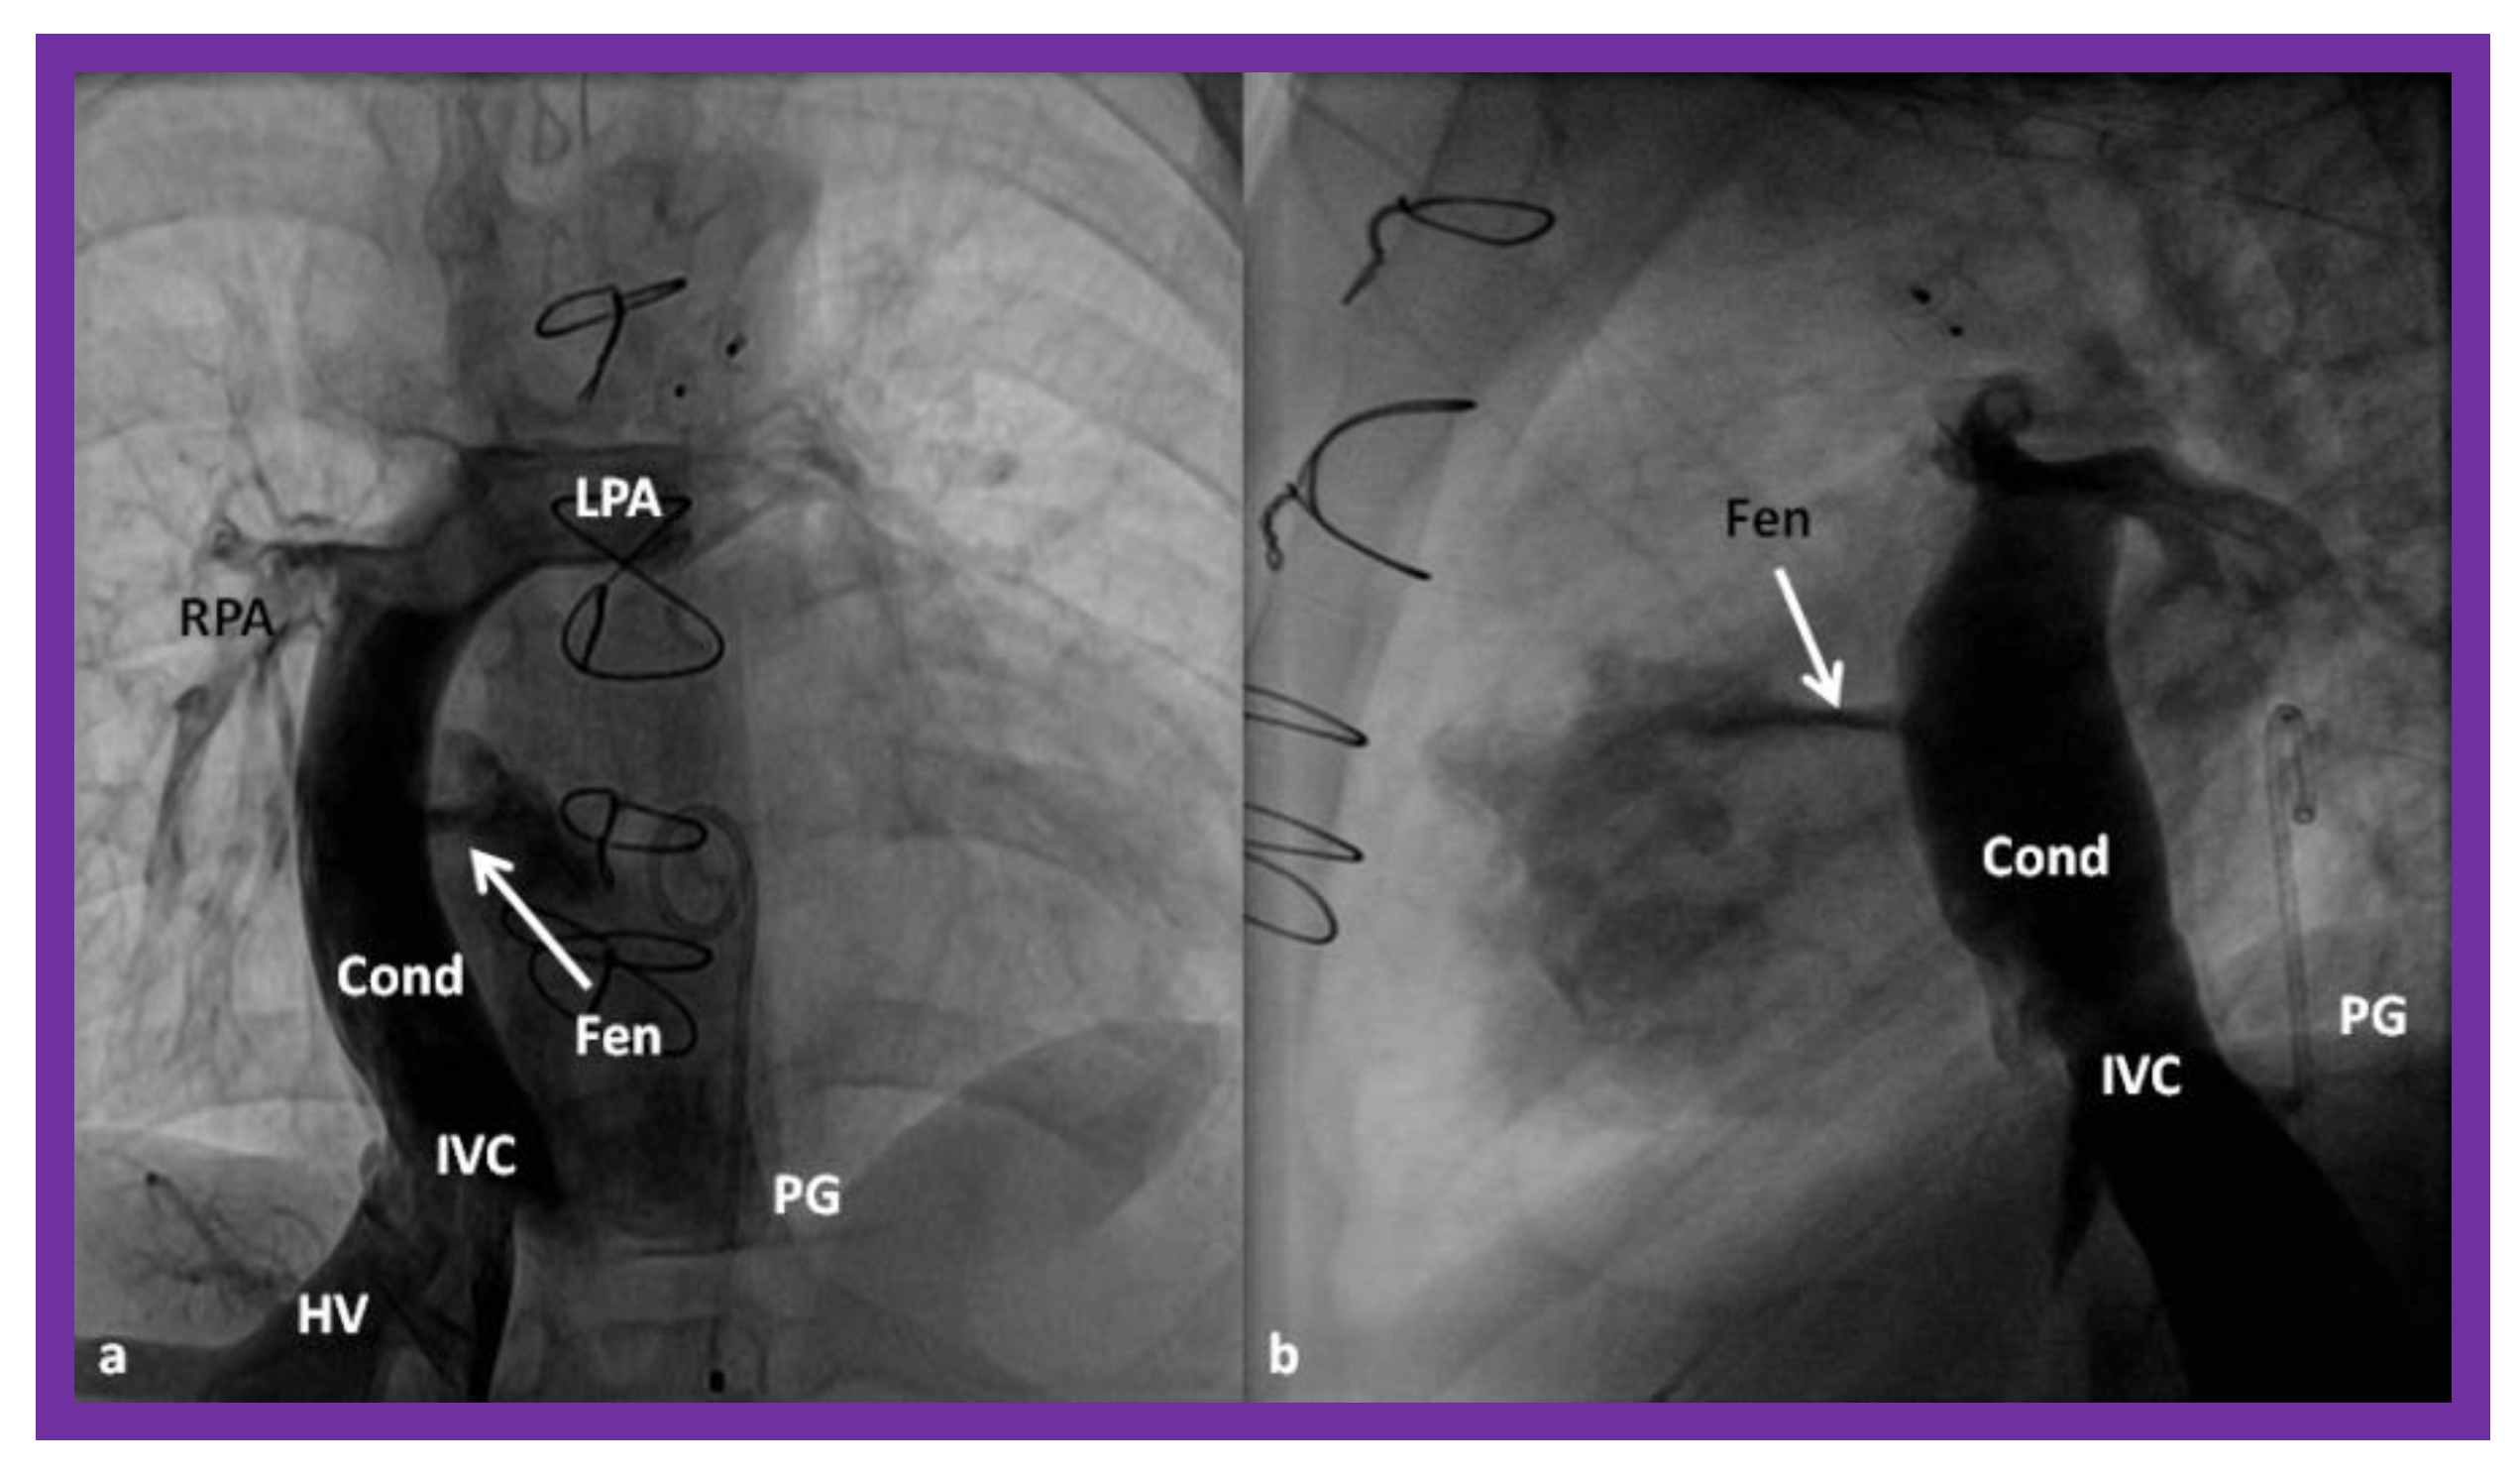

In the Stage IIIA, the TCPC may be accomplished by redirecting the IVC blood flow into the PA either by a lateral tunnel [77,78] or by an extra-cardiac, non-valved conduit (Figure 16) [79,80]. This surgery is typically carried out anytime from one to two years of age, frequently one year after the bidirectional Glenn. At the present time, the majority of surgeons favor an extra-cardiac conduit to achieve the final stage of Fontan. It also appears that most surgeons create a fenestration, 4–6 mm in size, between the conduit and the atria (Figure 16) [81]. Whereas creation of fenestration during the Fontan surgery was originally suggested for patients with high-risk [81,82], most surgeons and pediatric intensivists appear to opt for fenestration, because the creation of fenestration during the Fontan decreases mortality rate and lessens the morbidity during the immediate postoperative period [33].

Figure 16.

Cineangiographic frames in postero-anterior (a) and lateral (b) projections, illustrating Stage IIIA of the Fontan procedure in which the inferior vena caval (IVC) blood flow is diverted into the pulmonary arteries via a non-valve conduit (Cond). The flow via the fenestration (Fen) is shown by the arrows in a and b. HV, hepatic veins; LPA, left pulmonary artery; PG, pigtail catheter in the descending aorta; RPA, right pulmonary artery. Modified from Reference [33].